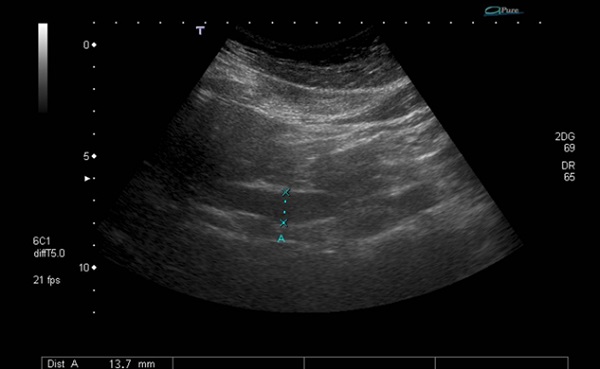

Adolescente de 14 años traída al Servicio de Urgencias por dolor en región centrotorácica de características opresivas de 24 horas de evolución, asociando náuseas en las últimas 12 horas. No presentaba antecedentes de interés, excepto un cuadro de 2 meses de evolución de vómitos de repetición tras la ingesta. Se encuentra a su llegada hemodinámicamente estable con constantes en rango y auscultación cardiopulmonar normal. En la exploración destaca dolor difuso a la palpación del abdomen con signo de Murphy positivo. El electrocardiograma realizado impresiona de ligero supradesnivel del ST en derivaciones laterales, por lo que se decide extraer analítica de sangre para valoración de troponinas y creatinquinasa (CK). No existía elevación de troponinas ni de CK, pero se apreció un patrón colestásico (ALT 54 U/l, AST 91 U/l, GGT 285 U/l, fosfatasa alcalina 113 U/l y bilirrubina 1,2 mg/dl). Ante este hallazgo, se solicita ecografía de abdomen en la que se aprecia colelitiasis sin signos de colecistitis y dilatación del conducto colédoco (de hasta 13 mm), sin lograr identificar la causa obstructiva por interposición de gas intestinal (Fig. 1).